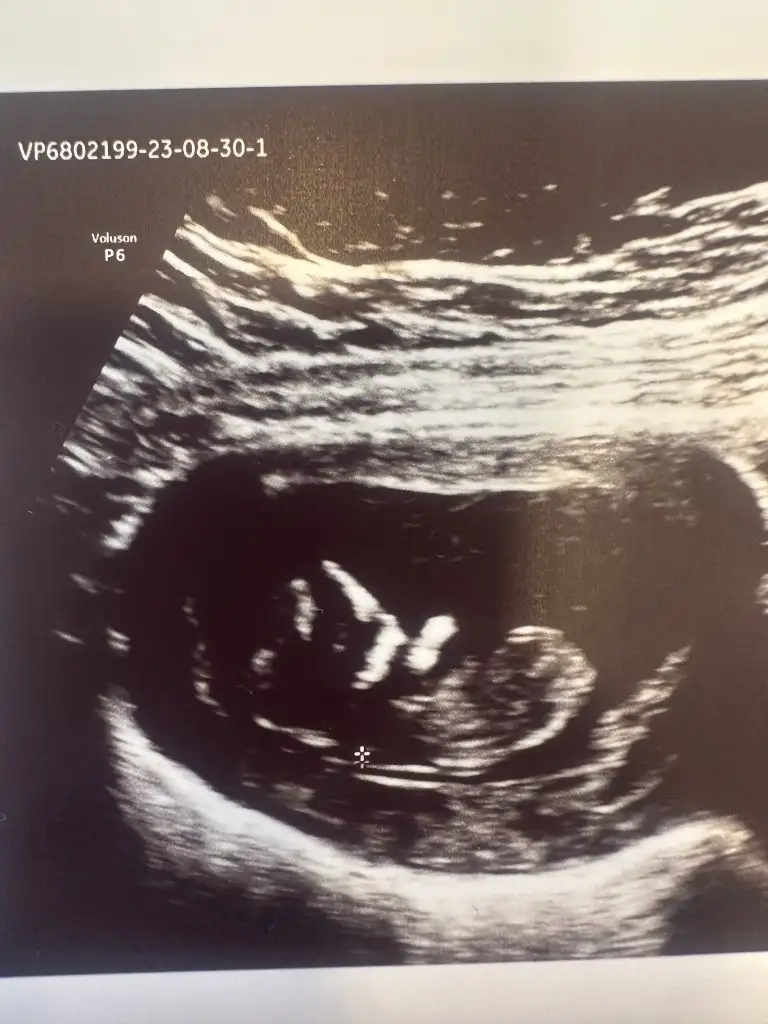

Selam kizlar.. anlayan varsa bi bakabilir mi benimkinede.. merak ediyorumda bebegim 11+5 ve karindan cekildi

Karından çekildiyse erkek

Kese şekli yuvarlaksa erkek diyorlar bunun ne kadar doğru olduğunu bilmiyorum, ama plasenta sağda ve sağ olunca erkek bebek demekmiş ramziye göre